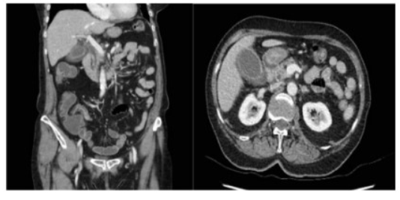

Paciente feminina, 72 anos, é trazida por familiares com história de dor abdominal de início há 5 dias, inicialmente periumbilical, inespecífica, associada a vários episódios de vômitos, hiporexia, febre e queda do estado geral. Hoje apresentou piora da dor e foi trazida pelos seus familiares devido à confusão mental. Nega colúria e acolia fecal. Nega sintomas urinários. Nega trauma. É hipertensa, diabética, portadora de fibrilação atrial e faz uso regular de enalapril, metformina, amiodarona e warfarina. Ao exame físico: mau estado geral, descorada, desidratada, taquipneica, anictérica, acianótica, febril. Bulhas cardíacas arrítmicas, taquicárdicas. Murmúrio vesicular presente bilateral, sem ruídos adventícios. Abdome distendido, mas depressível, doloroso difusamente, sem sinais de irritação peritoneal, com plastrão palpável em quadrante superior direito. Extremidades frias e mal perfundidas. Confusa, sonolenta, desorientada, com 12 pontos na escala de coma de Glasgow. Foi admitida em sala de emergência, aberto protocolo de sepse, realizado expansão com cristaloides, coletado culturas e lactato e iniciado antibioticoterapia empírica. Sinais vitais: PAM: 60 mmHg / FC: 125 bpm / FR: 26 ipm / T: 38,5°C / Sat O2: 85% em ar ambiente. Exames séricos: leucocitose 22.000 /mm3, amilase e lipase normais, provas de injúria hepática (AST e ALT) discretamente elevadas, sem sinais laboratoriais de obstrução canalicular. Lactato de admissão aumentado 3 vezes o valor de referência. Relação pO2/FiO2: 235. Sob suspeita de sepse de foco abdominal, foi submetida à tomografia com contraste abaixo. Assinale a principal hipótese diagnóstica.